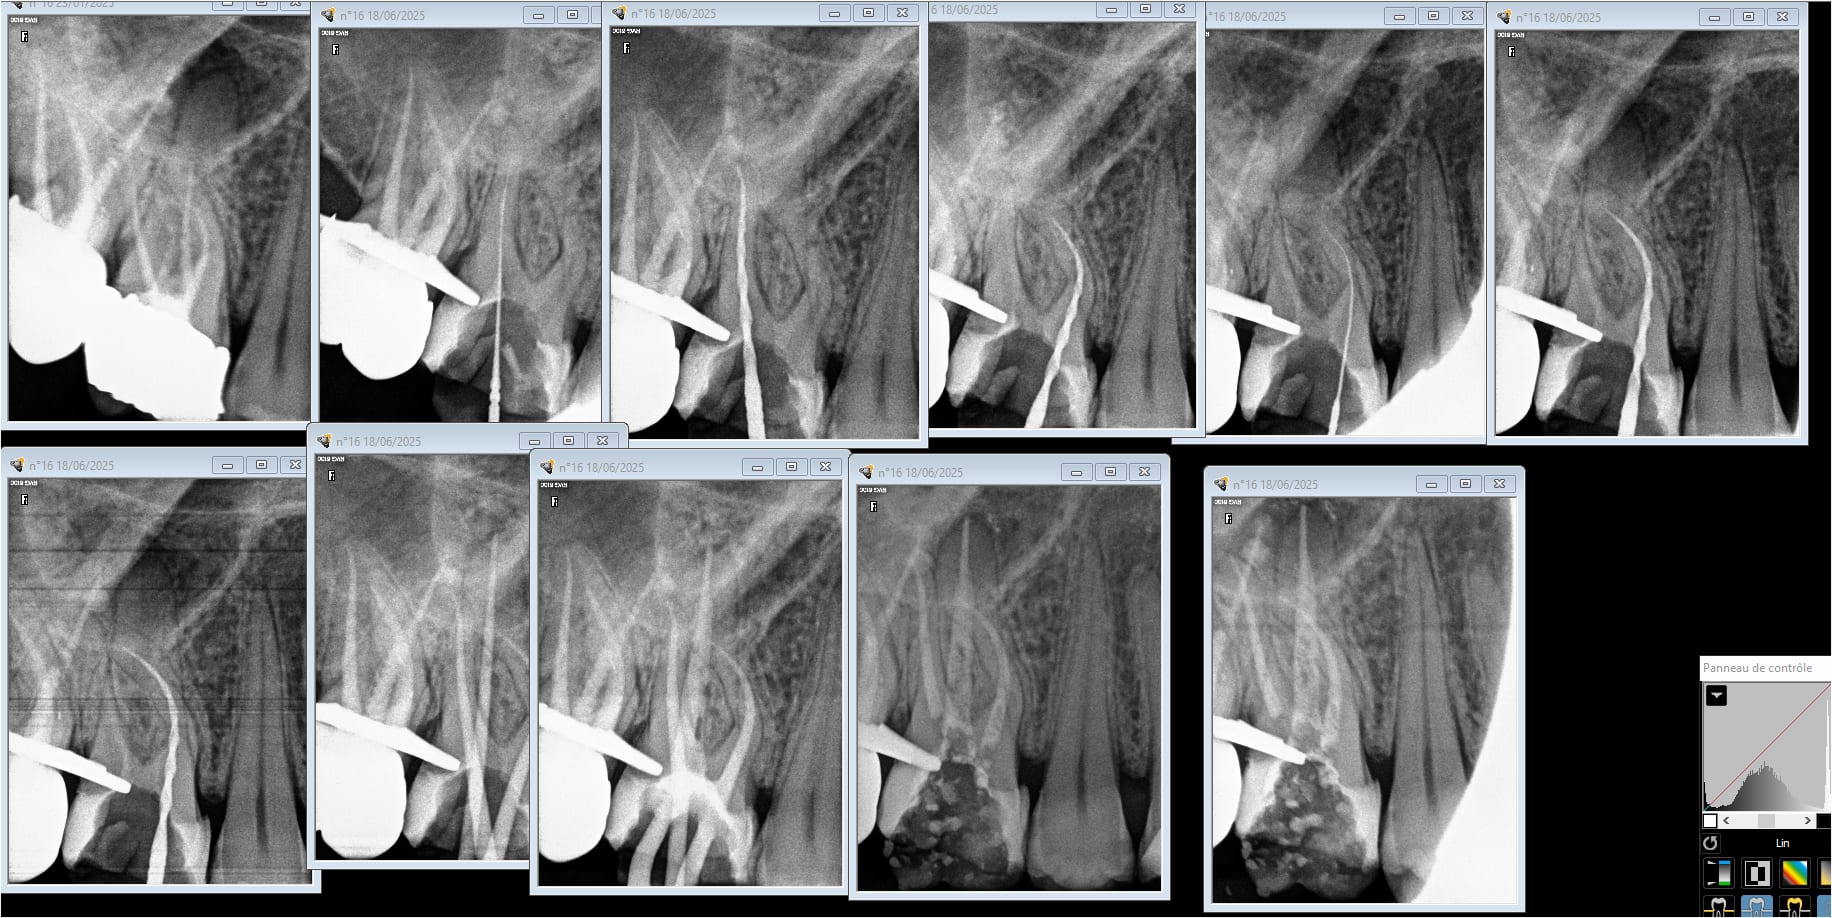

A 4 mains une endo molaire ca va pas plus vite quand tu as toutes les limes sur les contre angle endos déjà préparés . Ca va pas te faire avancer plus vite avec des limes manuelles dans des canaux et des RTE merdiques. Et encore ici j'ai pas insisté sur le MV2 tellement les autres m'ont fait chier.